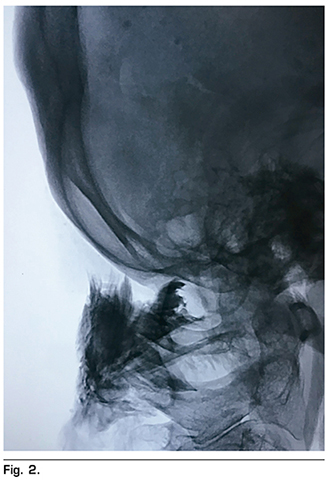

La técnica que se utilizó fue descrita por Racz y cols. (12), se localizaron mediante guía fluoroscópica a través de un arco C y en una posición anteroposterior las vértebras cervicales 1 y 2, posteriormente se rotó el equipo de arco en C a 90° para observar una proyección lateral, localizando las apófisis espinosas de las vértebras cervicales 1 y 2 (C-1 y C-2). Se eligió el punto de abordaje, localizado a 2 centímetros lateral izquierda de la protuberancia occipital mayor en la línea nucal superior, se infiltró piel cabelluda y tejido celular subcutáneo con lidocaína simple al 2 %. Posteriormente se introdujo una aguja espinal BD tipo Quincke 22 G 88 mm, en sentido cefalocaudal y lateromedial; de manera cuidadosa se avanzó a través de las capas fasciales musculares para evitar una lesión nerviosa o vascular (entre las que se encuentran la raíz nerviosa de C-1 o nervio suboccipital, raíz nerviosa de C-2 o tercer nervio occipital, el plexo cervical, la arteria cervical ascedente, la arteria o vena cervical profunda, y la arteria o vena vertebral) hasta hacer contacto con apófisis espinosa de C-2 (Figura 1); se retiró 2 mm y se aspiró para verificar punción inadvertida de vasos o duramadre. Una vez confirmado que no hubo salida de sangre o líquido cefalorraquídeo, se administraron 4 ml de medio de contraste no iónico, observando una difusión hacia la región occipital de forma triangular (triángulo formado por los músculos oblicuo mayor, oblicuo menor, recto posterior de la cabeza y el semiespinoso de la cabeza) (Figura 2). Ya corroborado el objetivo terapéutico, se aspiró nuevamente y se administraron 5 ml de bupivacaína (25 mg) con metilprednisolona no soluble (40 mg) aforados en solución salina hasta un total de volumen de 10 ml en el lado afectado, observando una adecuada disección de los planos musculares antes descritos en la imagen fluoroscópica. Se retiró aguja, se pasó a la paciente a recuperación sin incidentes, ni complicaciones.